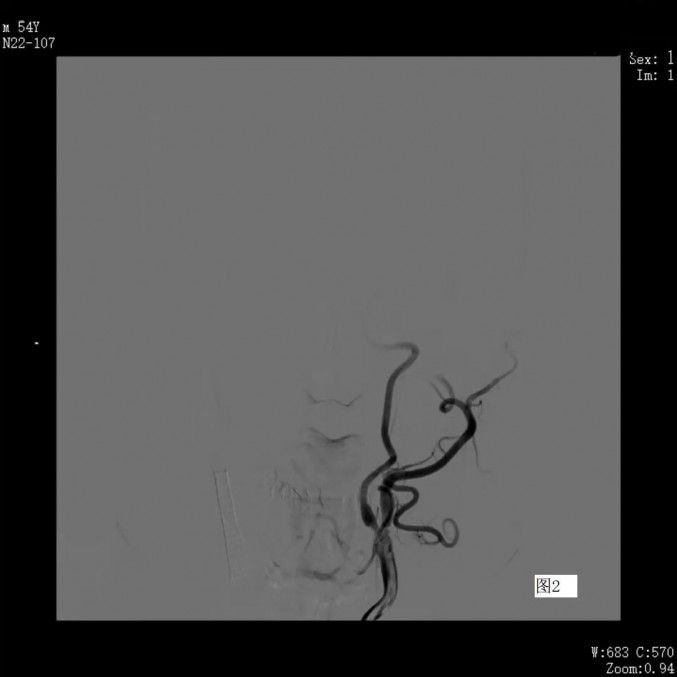

经右侧桡动脉造影管顺利进入左侧颈总动脉

左侧颈内动脉开口处仍重度狭窄